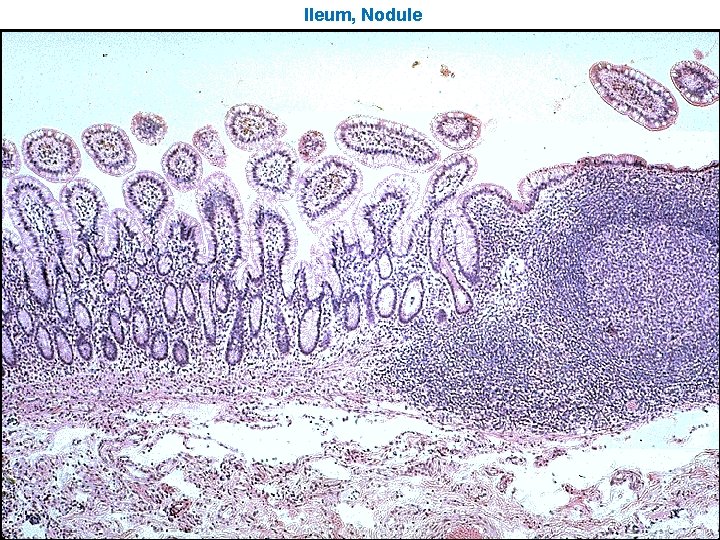

Lymphoid Nodules (Follicles): These occur in all lymphatic aggregates except the thymus. Active (lymphocyte-producing) nodules each have a darkstaining periphery, or mantle zone, that contains tightly packed small lymphocytes, and a light-staining core, or germinal center, that contains numerous immunoblasts (lymphoblasts), ie, lymphocytes stimulated by antigens to enlarge and proliferate. The lighter staining reflects the increased cytoplasmic volume and decreased nuclear heterochromatin that accompany lymphocyte activation.

Ileum, Nodule

Lymphatic Nodule n n “Non-capsulated” Single or aggregated Independent OR parts of lymphoid organs Outer dark zone n n (Corona or cap) Germinal centre